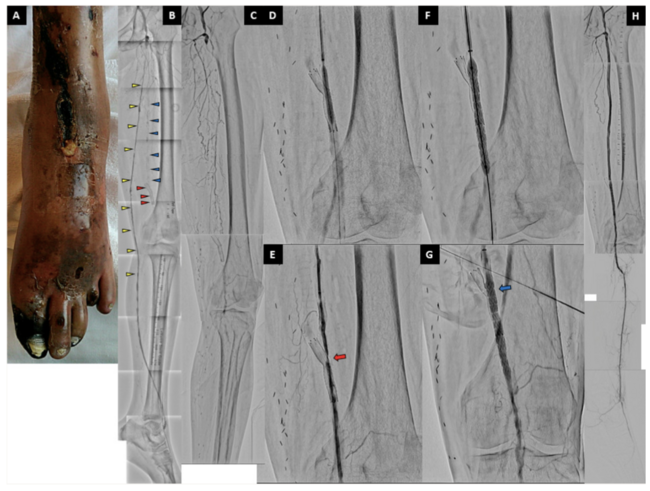

A 57-year-old woman with critical limb-threatening ischemia (CLTI) of the left lower leg underwent endovascular therapy (Figure 1A). She had undergone a femoropopliteal (F-P) bypass for treatment of chronic total occlusion (CTO) of the superficial femoral artery (SFA) four years prior. However, its occlusion occurred. Thus, a self-expandable stent was placed at the F-P bypass anastomosis three years previously. Nevertheless, the F-P bypass occluded, and CLTI recurred. Therefore, distal bypass (common femoral artery [CFA] – anterior tibial artery [ATA]) was performed one year prior (Figure 1B).

However, occlusion recurred three months previously. Lower-limb arteriography revealed an occluded native SFA, F-P bypass, and distal bypass (Figure 1C, Video). Using the distal puncture technique, we crossed the wire to the dorsalis pedis artery (DPA). We dilated the CTO of the SFA at the F-P bypass anastomosis jailed by the stent. However, we could not achieve sufficient dilation because the wire passed through the stent strut (Figure 1D, E, Video). Notably, the lesion could not be expanded without destroying the stent strut. Therefore, we used a balloon-expandable covered stent (VBX, Gore-Tex) (Figure 1F, Video). Sufficient dilation was observed (Figure 1G). Subsequently, we placed self-expandable stents in the proximal and middle SFA (Video). Additionally, the ATA was dilated using a noncompliant balloon (Video). Finally, we obtained sufficient blood flow to the DPA (Figure 1H, Video). In such cases, no other alternatives exist for sufficient expansion of the CTO of the SFA at the F-P bypass anastomosis. While placement of balloon-expandable covered stents in the SFA has not been adapted, it can be effective for sufficient dilation and limb salvage.